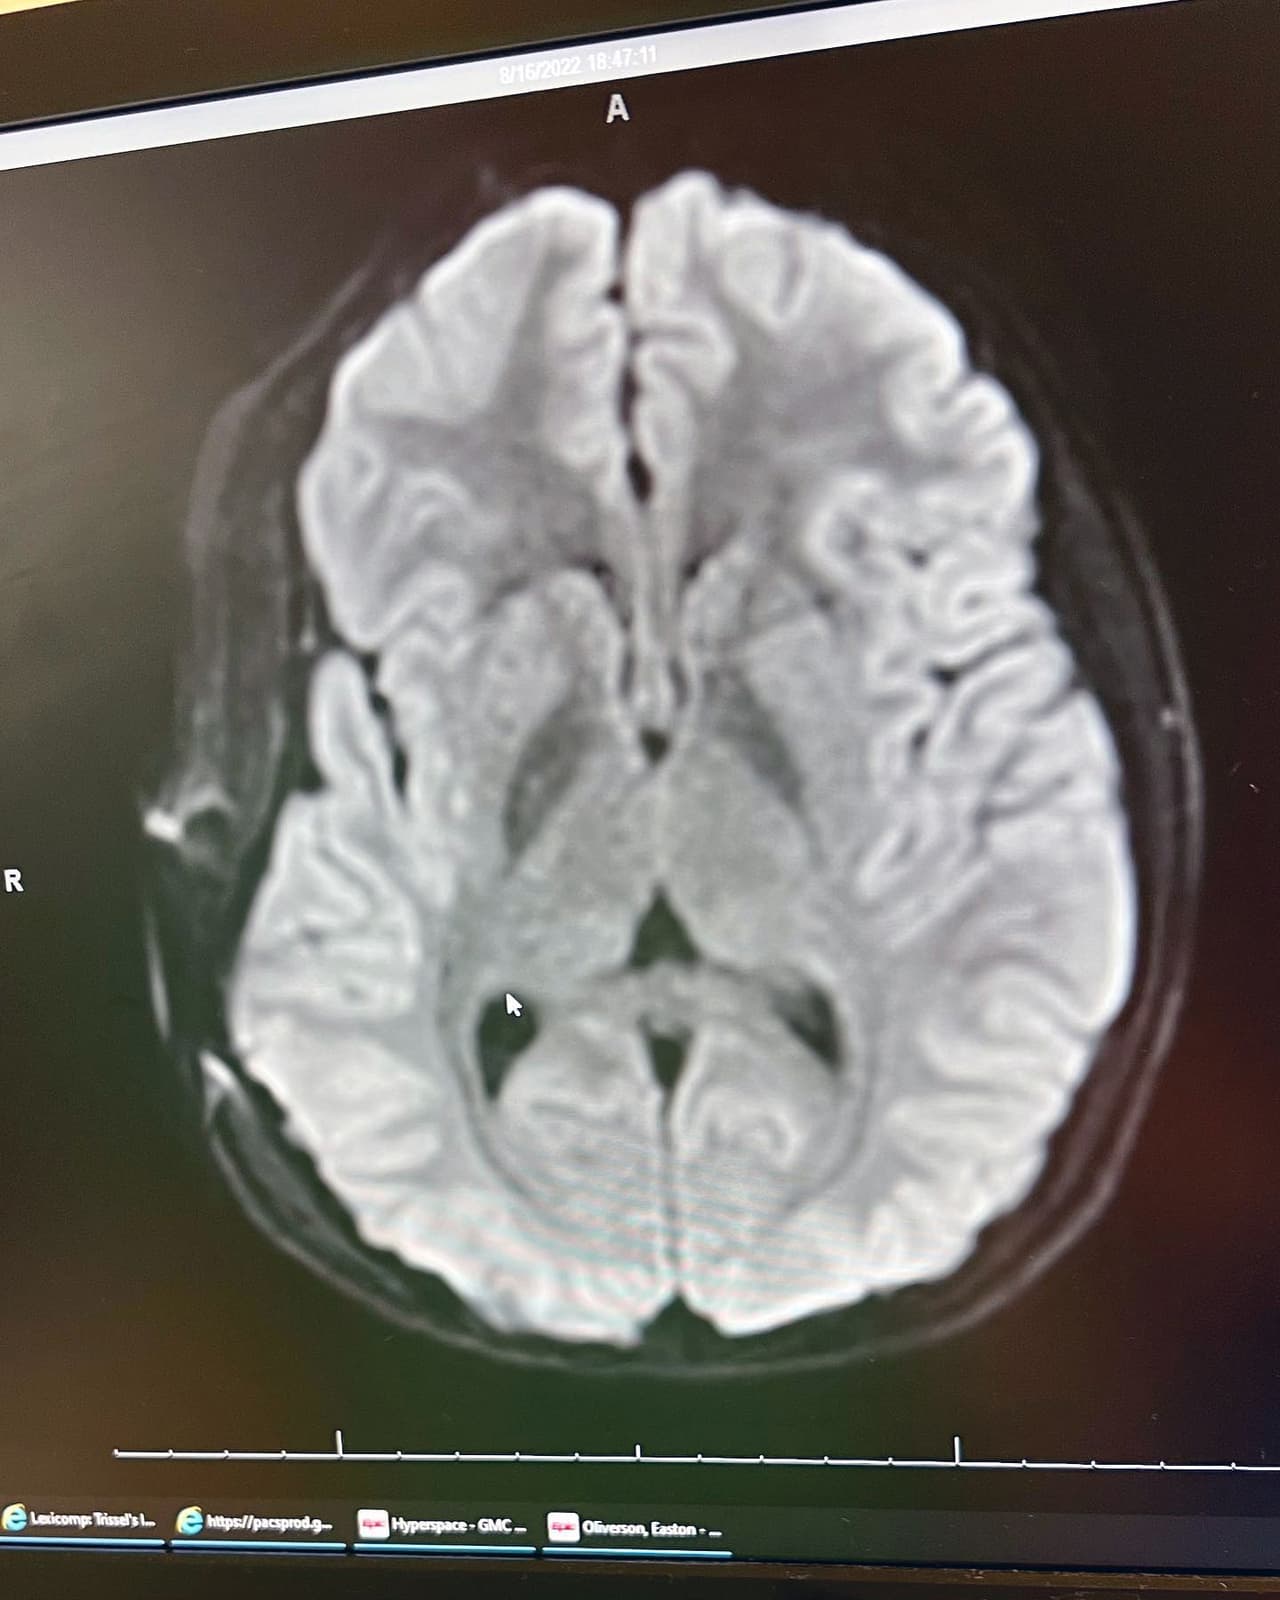

El pequeño lanzador sufrió de una perforación en una arteria, lo que causó una hemorragia cerebral. Los médicos retiraron parte de su cráneo para aliviar la inflamación y lograr operarlo de emergencia.